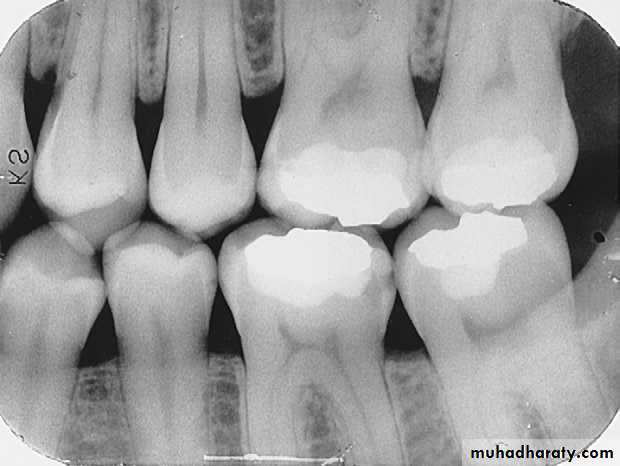

On a dental image, interproximal caries is typically seen at or just below (apical to) the contact point.Interproximal caries can be classified according to the depth of penetration of the lesion through enamel and dentin. Interproximal carious lesions can be classified as incipient, moderate, advanced, and severe.

Interproximal Caries

(Incipient)I

Up to half the thickness of enamel

Usually not restored unless patient has high level of caries activity (high risk). Treat with fluoride.

Incipient Interproximal Caries

An incipient carious lesion on the distal surface of the mandibular second premolar.

M

(Moderate)

More than halfway through the enamel (up to DEJ)

Moderate Interproximal Caries

A moderate carious lesion on the distal surface of the mandibular second premolar